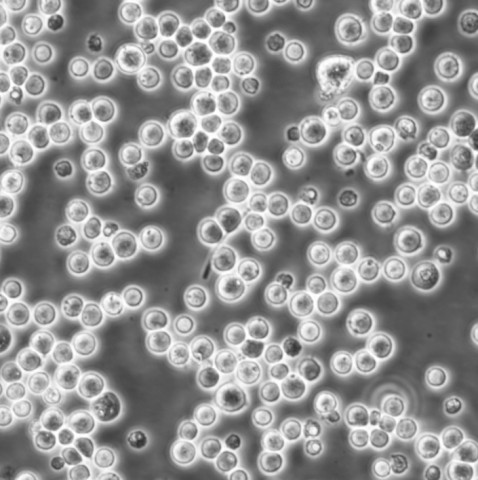

CCRF CEM Cells人急性淋巴细胞白血病T淋巴悬浮细胞系(提供全部细胞STR鉴定图谱)

背景信息:G.E. Foley 等人建立了类淋巴母细胞细胞株CCRF-M。 细胞是1964年11月从一位四岁白人女性急性淋巴细胞白血病患者的外周血白血球衣中得到。此细胞系从香港收集而来。

生长特性:悬浮生长

形态特性:淋巴母细胞样